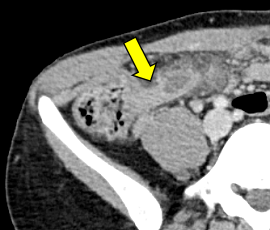

[急性虫垂炎] 手術:腹腔鏡下虫垂切除術

急性腹症のため救急受診。精査の結果、急性虫垂炎および限局性腹膜炎と診断。緊急手術(腹腔鏡下虫垂切除術)を施行した。病理診断結果は急性虫垂炎であった。

CT画像